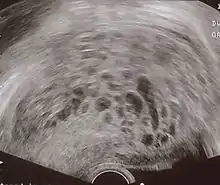

The diagnosis is strongly suggested by ultrasound (sonogram), but definitive diagnosis requires histopathological examination. On ultrasound, the mole resembles a bunch of grapes ("cluster of grapes" or "honeycombed uterus" or "snow-storm").[14] There is increased trophoblast proliferation and enlarging of the chorionic villi, and angiogenesis in the trophoblasts is impaired.[15]